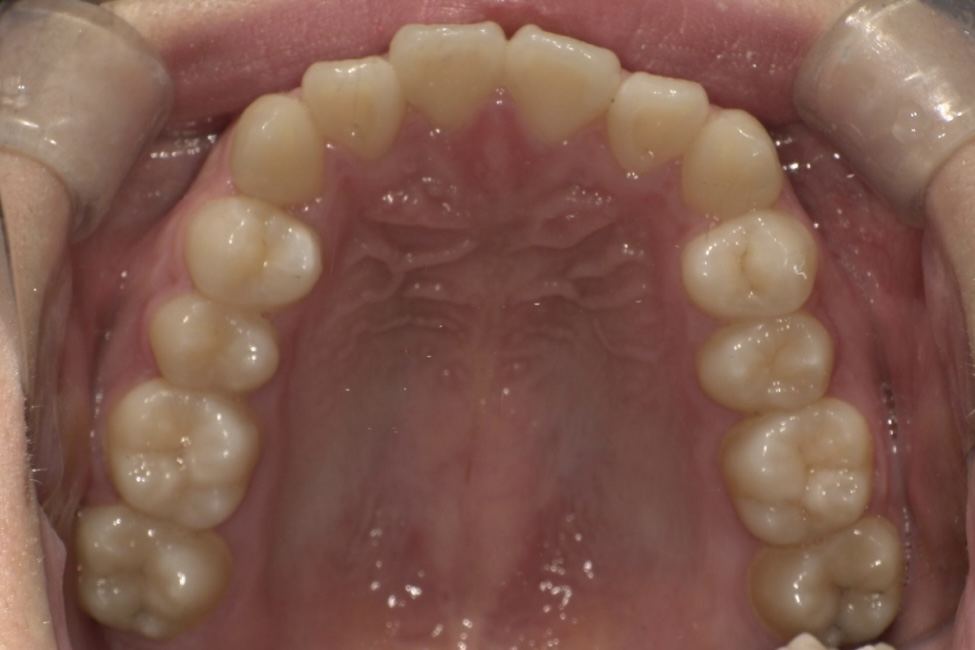

BEFORE

大学生の女性の患者さまで、ガタガタした歯並びをできるだけ痛みの少ない方法で整えたいとご相談に来院されました。

治療は、マウスピース矯正インビザラインにて矯正治療を行い、歯列全体のバランスを考慮しながら計画を立てました。治療期間は1年4ヶ月で、歯並びがきれいに整っています。